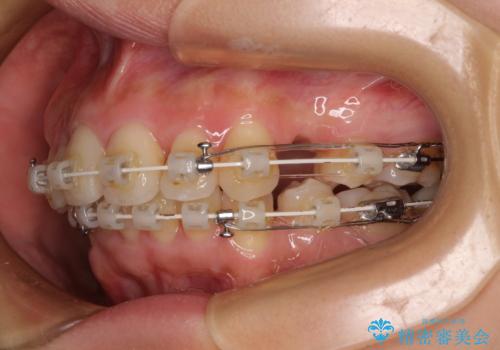

- 矯正装置

- 審美装置

上下左右第一小臼歯4本を抜歯し、ワイヤー装置にて矯正治療を行うこととしました。

想像以上に咬合力が強く、抜歯したスペースを閉じきるまでに長期間を要することとなりました。